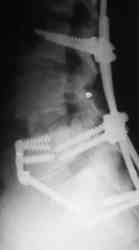

Если позволите, некоторые теоретические соображения по результатам и показаниям. Сегодня все знают как оперировать позвоночник по поводу любых "напастей". Когда после операции боли остаются приходит время вспомнить о том, что морфологический субстрат боли при полисегментарной саногенетической реакции патологического типа, каким является остеохондроз и другие спондилогенные изменения дегенеративно-дистрофического характера, точно установить, как правило, невозможно. Аномалиям развития здесь особенно не повезло. Например, если у пациента протрузии на нескольких уровнях, дегенеративный стеноз и сакрализация - лечат сакрализацию т.к. она "режет глаз" специалисту. Соответственно и эффект от вмешательства на уровне "не навредили". Специальные методы исследования мало что дают в этом плане, а МРТ, вообще, годится только для обоснования необходимости операции при разборе жалобы. Поэтому вначале рекомендую лечебно-диагностические тест-блокады. Если эпидуральная по Катлену через день (результат оценивать после 3-5 блокад) снимает жалобы - оперировать не стоит. Если локальная боль остается - прицельную паравертебральную в зону неоартроза - исчезновение боли показание не к операции, а к повторному курсу через 3-6 мес. Стойкий локальный монолатеральный болевой синдром - повод задуматься об операции. Но, как правило, она должна быть более обширной чем просто резекция поперечного отростка и санировать и другие проблемы. "Золотой стандарт" тут пока передне-задняя фиксация в различных ее вариантах в зависимости от конкретного случая. Попытки "располовинить" спондилодез в отношении чистой изолированной транспедикулярной фиксации в пятилетнем наблюдении не выдерживают критики. Передняя изолированная фиксация пластинами с аутокостным спондилодезом дает хорошие результаты (пример на фото 4)

при условии дополнения задним релизом для декомпрессии сосудисто-нервных образований ( ну а тогда почему уже и конструкцию сзади не поставить? фото 5).